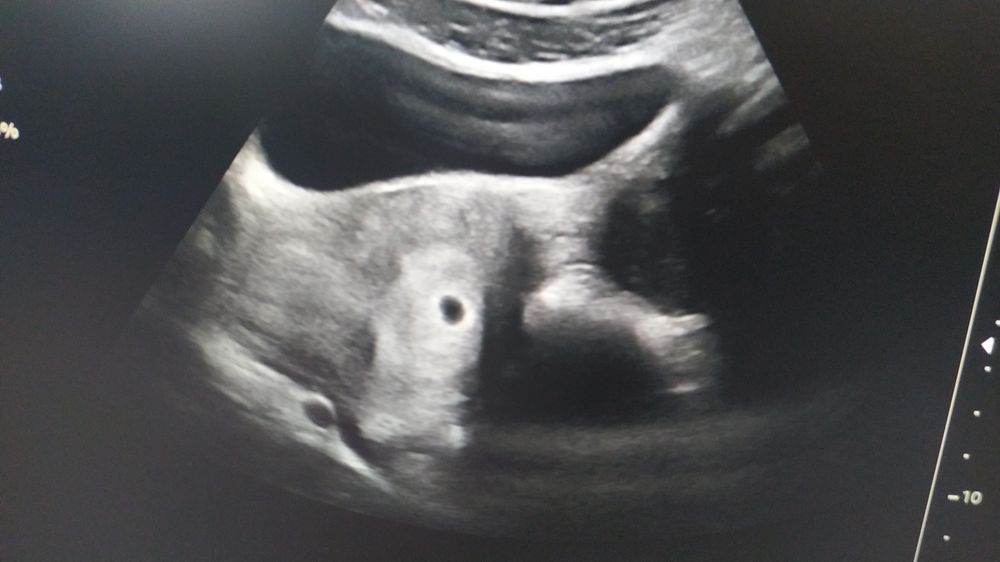

2 марта эхо показало только что-то подозрительное, днем тест опять положительный

Теперь хочу понять, если плод маленький, то поэтому эхо его не показало, или есть другая причина?

Вы имеете в виду, что по УЗИ не видно? Скорее всего рано пошли. Можете сдать кровь на Хгч, только от 1000-1500 единиц на УЗИ можно увидеть плодное яйцо.

Ну конечно, ведь вашему эмбриону не было 4 недель даже. Вы Увидите его на 6й неделе хотя бы.

В три недельки после зачатия еще не видно лялю - у меня так было, пойдите еще раз на узи через две недельки и уже будет виден эмбрион и сердцебиение

, что беременна (5 неделья) спасибо всем 😘